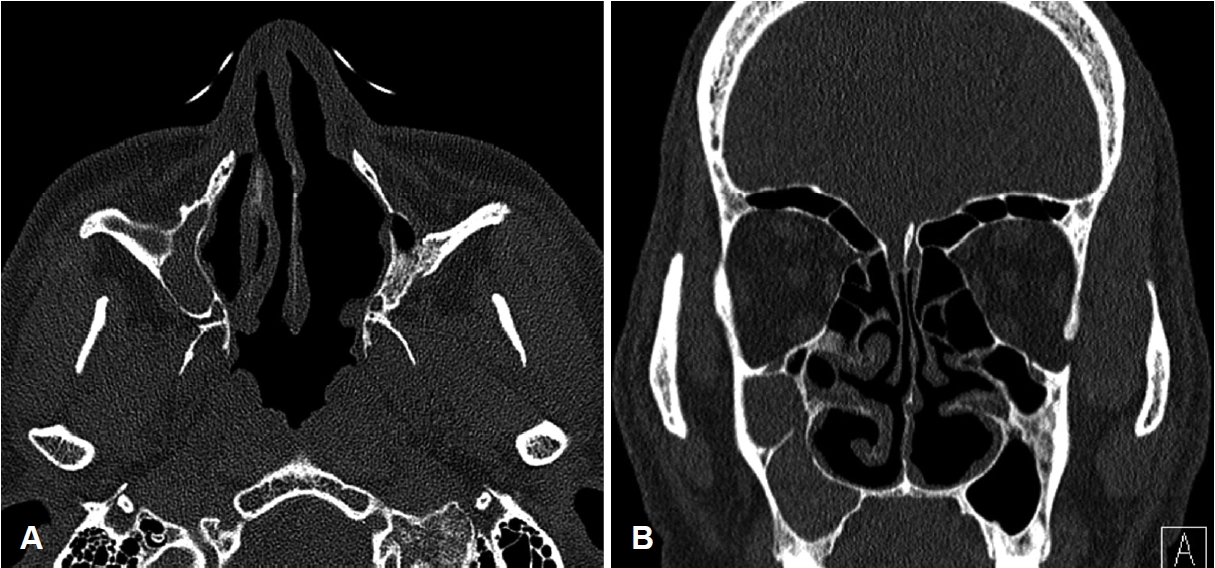

방 법수술 전 평가수술 전 평가과정에서 비내시경 검사를 통해 환측 하비갑개가 건측에 비해 심한 결손과 위축이 있는지 확인하고 정확한 문진을 통해 코 수술 과거력을 파악하였다(Fig. 1). 알레르기 검사, 후각검사를 시행하였으며 증상의 정도를 평가하기 위한 sino-nasal outcome test (SNOT-22) 설문지를 시행하였다. 전산화단층촬영(CT)을 통해서 환측 하비갑개가 건측에 비해 결손된 부분이 있는지, 다른 해부학적 이상이 없는지 다시 확인하였다(Fig. 2). 빈코 증후군의 진단에 도움이 되는 cotton test를 시행하였으며 생리식염수를 적신 솜을 비강 내에 넣어둔 상태에서 증상이 호전되는지 확인하였다.

NotesAuthor Contribution Conceptualization: Sang Jae Lee, Hyung Gyun Na. Data curation: Sang Jae Lee, Yoon Seok Choi. Formal analysis: Chang Hoon Bae, Hyung Gyun Na. Investigation: Yoon Seok Choi, Chang Hoon Bae. Methodology: Sang Jae Lee, Hyung Gyun Na. Project administration: Yong-Dae Kim, Chang Hoon Bae. Resources: Yong-Dae Kim, Si-Youn Song. Supervision: Hyung Gyun Na. Visualization: Sang Jae Lee, Si-Youn Song. Writing—original draft: Sang Jae Lee. Writing—review & editing: Sang Jae Lee, Hyung Gyun Na. Fig. 1.Pre operative nasal endoscopic view shows defect and atrophy at left inferior turbinate compared with right inferior turbinate. Right (A) and left (B). Fig. 2.Pre operative CT scan shows defect and atrophy at left inferior turbinate compared with right inferior turbinate. Axial (A) and coronal (B). Fig. 3.Inferior turbinate reconstruction procedures with autologous costal cartilage graft. Block insertion at left nasal floor (A), augmentation graft with diced and crushed costal cartilage mixed with glue (B), and intra operative nasal endoscopic view shows well-reconstructed and regular surface at left inferior turbinate (C). *indicates the location where the reconstruction was done. REFERENCES1. Chhabra N, Houser SM. The diagnosis and management of empty nose syndrome. Otolaryngol Clin North Am 2009;42(2):311-30, ix.